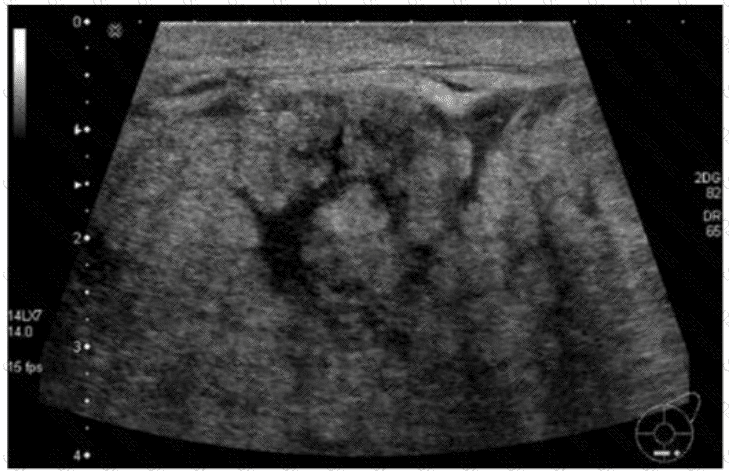

Which condition is demonstrated in this image?